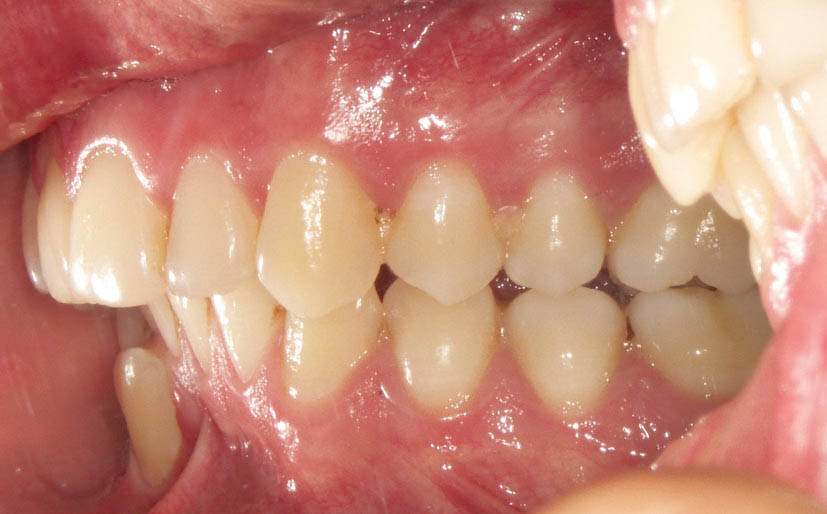

شکل 21-2: رابطه کلاسII مولری

شکل 22-2: رابطه کلاسII مولری

تقریباً بیش از 40درصد افراد جامعه بیماران کلاسII هستند (شکل 21-2 و 22-2).